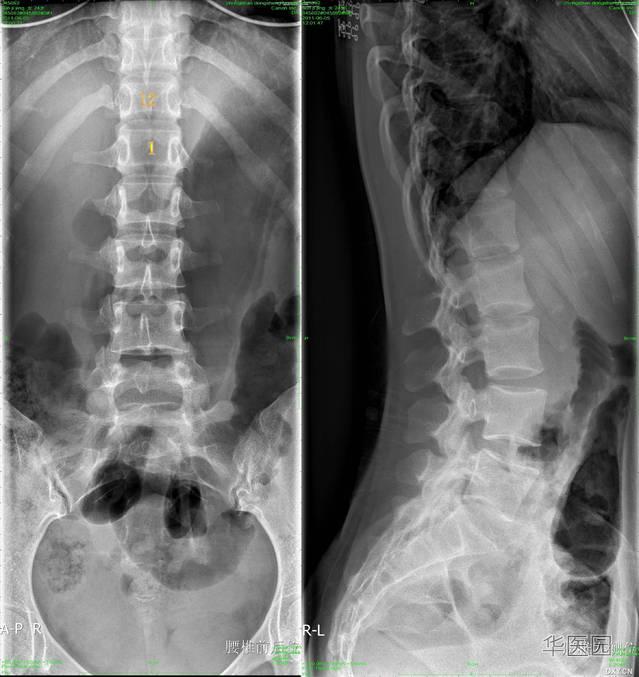

腰椎隐裂

箭头所示为第一骶椎隐性脊柱裂

诊断 诊断 脊柱x 线平片和ct 均能清晰显示椎管畸形,棘突及椎板缺损